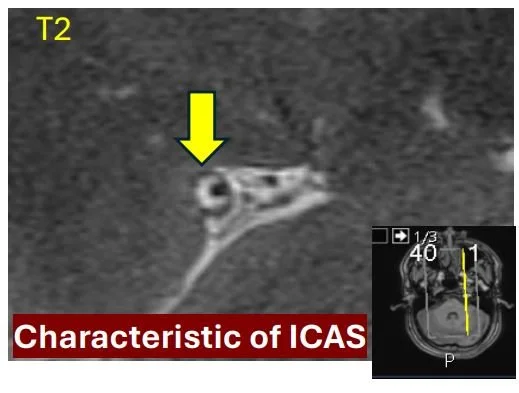

Emerging Concept of Intracranial Arterial Diseases: The Role of High Resolution Vessel Wall MRI (Jan 2024)

We review the embryology of the intracranial arteries, spectrum and vessel wall imaging appearances of intracranial arterial diseases and highlight future research directions on understanding the temporal profile of VWI findings and developing quantitative interpretative approaches.

MR Imaging for Intracranial Vessel Wall Imaging: Pearls and Pitfalls (May 2023)

We review the clinical applications for intracranial VWI and interpretive pearls and technical pitfalls for this innovative imaging technique.

Current Clinical Applications of Intracranial Vessel Wall MR Imaging (Oct 2021)

We review vessel wall MR imaging (VWI) features of different intracranial vasculopathies and show illustrative clinical cases.